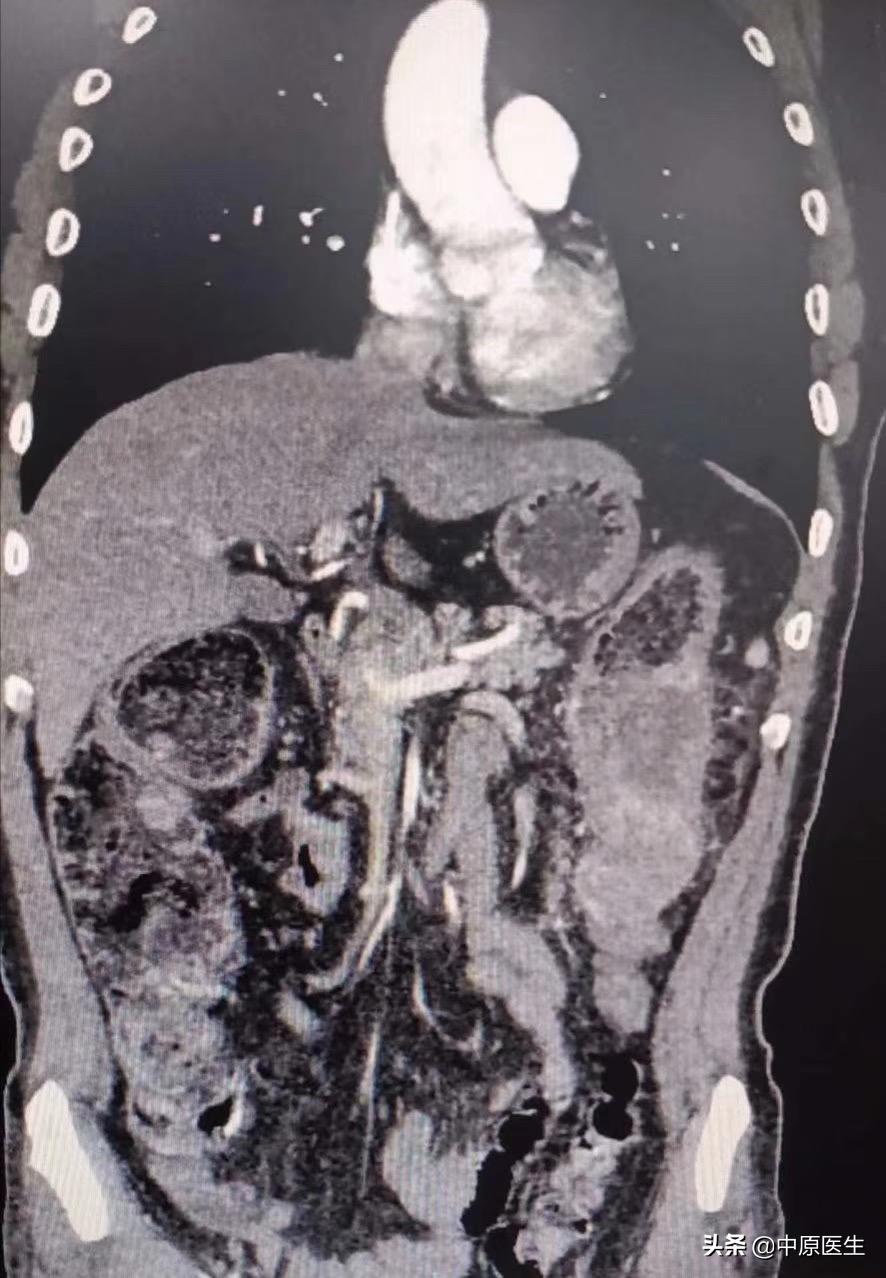

近1周来,患者腹胀进行性加重,体检发现患者腹胀如鼓。做腹部、盆腔ct:降结肠占位较前增大、重度狭窄,横结肠以上明显扩张、梗阻。经对症治疗效果欠佳,究竟该怎么办?

经过会诊,我们介入科刘建文教授团队决定通过介入方法帮助患者解决肿瘤引起梗阻的问题。25日,在导管室行局麻下消化道造影+降结肠球囊扩张+经肛型肠梗阻导管置入术。术中透视见腹部膨大,肠管明显扩张,膈肌上移。让患者取截石位仰卧,充分润滑、局麻后,我们送入超滑导丝、直径不到1mm的导管,反复尝试导丝通过闭塞处、送至横结肠脾曲处,但导管无法跟进,为了保留150cm的超滑导丝,将100cm的直径不到1mm导管分段剪断、依次撤出,再送入直径2mm的指引导管,再送入一根260cm的超滑加硬导丝,送至横结肠内,依次用10mm球囊、肠梗阻导管的扩张器反复扩张狭窄处,肠梗阻导管仍无法通过,再次同轴送入双导丝,应用16mm球囊多次扩张后,顺利把肠梗阻导管送至横结肠内,充盈导管头端球囊,将肠梗阻导管头端固定于降结肠梗阻处上方;淤积的肠气和部分肠液、粪便排入引流袋内,病人腹胀减轻。术中反复交换各种导丝、导管,带出不少臭屁、臭粪便。整个手术间都是不可描述的气味、手术台不忍直视。